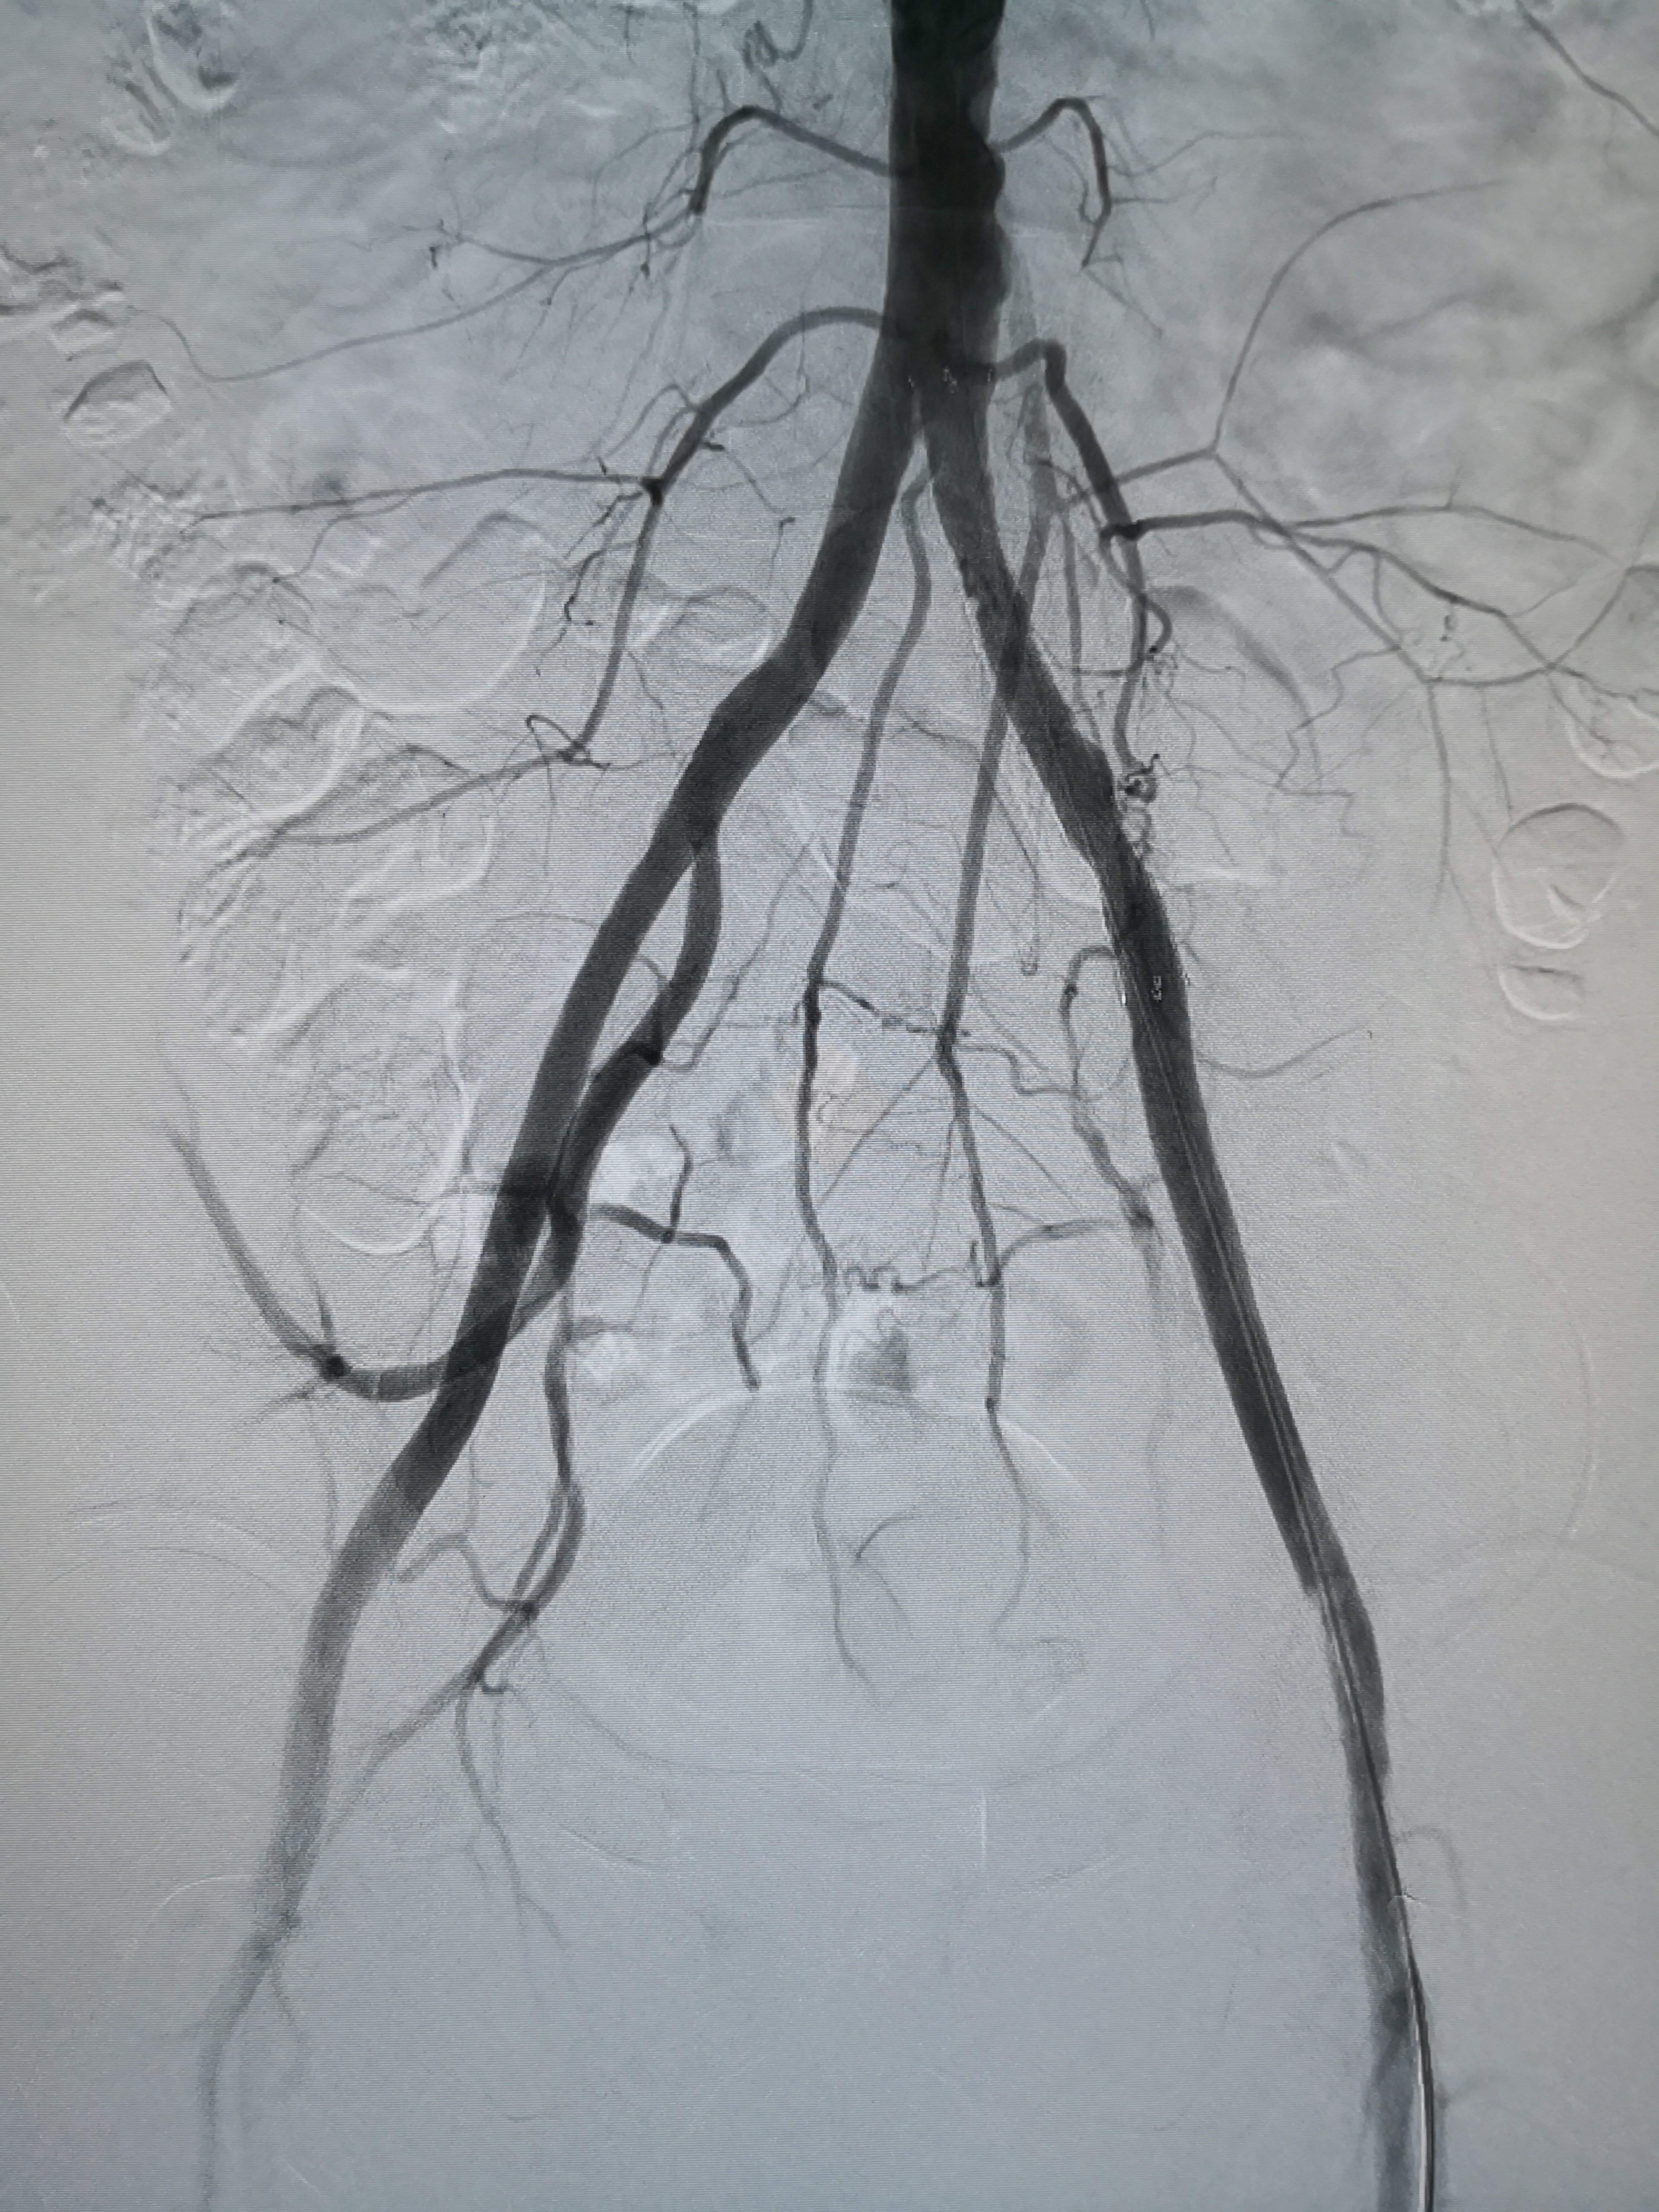

f:腹主动脉下段急性闭塞e:右侧ica取出的血栓d:取栓后右侧ica造影正位